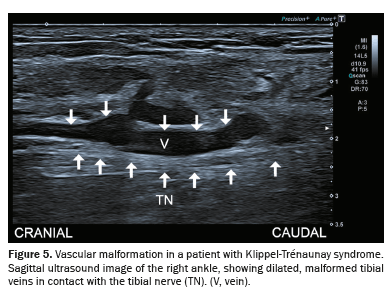

Varicose plantar vein

Varicose plantar veins are among the most common vascular causes of TTS. These veins are typically dilated (diameter ≥ 5 mm), tortuous, and associated with signs of venous stasis. Their dilation often becomes more pronounced when the patient is in a standing position(1,7), as illustrated in Figure 1.